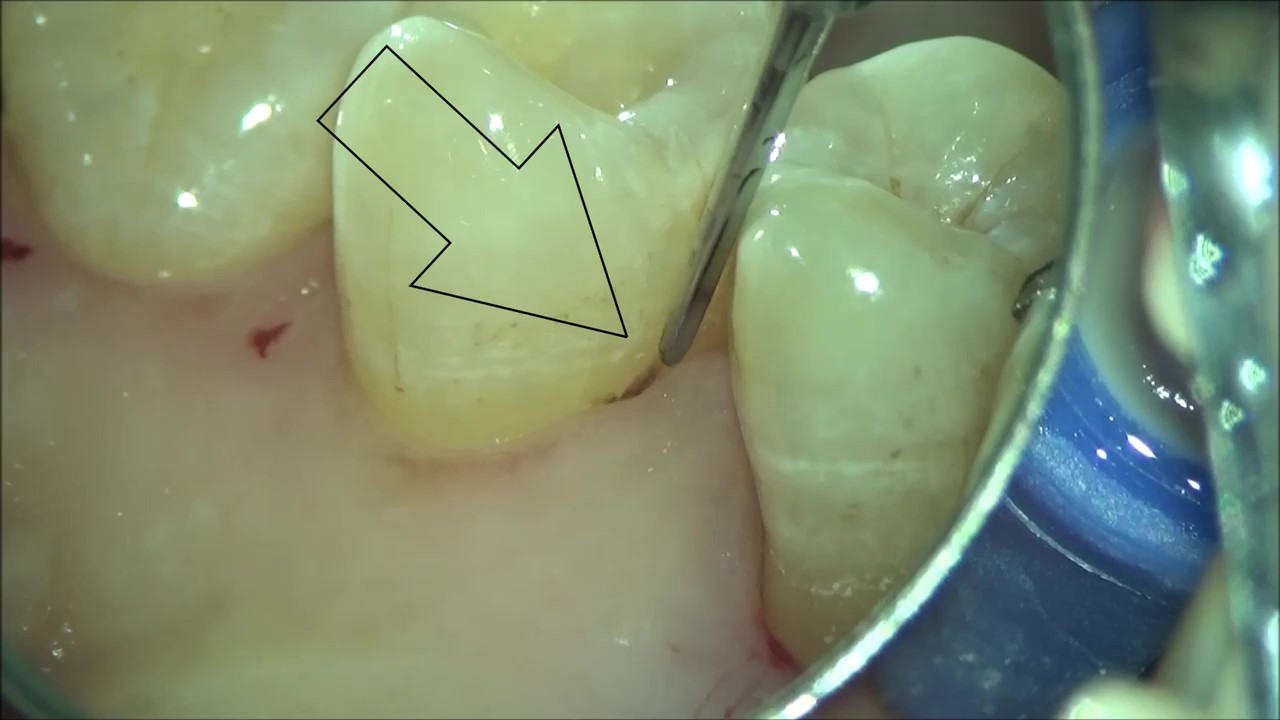

マイクロスコープを使った歯科治療

こんにちは! 南館歯科クリニックの歯科衛生士 山崎です。 マイクロスコープについてのご紹介をします(*^_^*) マイクロスコープは、 微小な物体を視覚的に拡大し、肉眼で見える大きさに拡大する装置です…